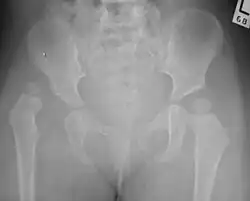

Congenital dislocation of the left hip in an elderly person. Closed arrow marks the acetabulum, open arrow the femoral head.